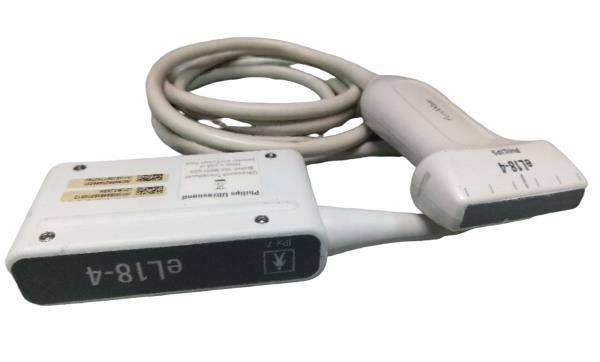

Model: RUS-6000A

Brand: Carejoy

![Digital 3D Ultrasound Scanner Convex + Linear 2Probe/Transducers +Oximeter [DHL] 190891435651 DIAGNOSTIC ULTRASOUND MACHINES FOR SALE](http://ultraultrasound.com/cdn/shop/products/s-l1600_55eda9f8-0657-42e5-b08f-fb450561b305.jpg?v=1571451481&width=562)

![Digital 3D Ultrasound Scanner Convex + Linear 2Probe/Transducers +Oximeter [DHL] 190891435651 DIAGNOSTIC ULTRASOUND MACHINES FOR SALE](http://ultraultrasound.com/cdn/shop/products/s-l1600_a77dd9e6-c605-475e-b3f1-9f86fc93dbb9.jpg?v=1571451481&width=800)

![Digital 3D Ultrasound Scanner Convex + Linear 2Probe/Transducers +Oximeter [DHL] 190891435651 DIAGNOSTIC ULTRASOUND MACHINES FOR SALE](http://ultraultrasound.com/cdn/shop/products/s-l1600_99c50fa2-36fe-4a5b-bcf7-6ee7a0bac49b.jpg?v=1571451481&width=800)

![Digital 3D Ultrasound Scanner Convex + Linear 2Probe/Transducers +Oximeter [DHL] 190891435651 DIAGNOSTIC ULTRASOUND MACHINES FOR SALE](http://ultraultrasound.com/cdn/shop/products/s-l1600_d50ffb69-35d9-4e4d-a2f5-fd83f8b897dc.jpg?v=1571451481&width=500)

![Digital 3D Ultrasound Scanner Convex + Linear 2Probe/Transducers +Oximeter [DHL] 190891435651 DIAGNOSTIC ULTRASOUND MACHINES FOR SALE](http://ultraultrasound.com/cdn/shop/products/s-l1600_e2646f33-3bdd-4c03-a93f-5ecff438ba60.jpg?v=1571451481&width=500)

![Digital 3D Ultrasound Scanner Convex + Linear 2Probe/Transducers +Oximeter [DHL] 190891435651 DIAGNOSTIC ULTRASOUND MACHINES FOR SALE](http://ultraultrasound.com/cdn/shop/products/s-l1600_73c5e27c-235b-4093-a5c8-da4c1fd871e6.jpg?v=1571451481&width=500)

![Digital 3D Ultrasound Scanner Convex + Linear 2Probe/Transducers +Oximeter [DHL] 190891435651 DIAGNOSTIC ULTRASOUND MACHINES FOR SALE](http://ultraultrasound.com/cdn/shop/products/s-l1600_65d7ce40-ffb2-4c36-b75e-a0711be5b0e9.jpg?v=1571451481&width=800)

![Digital 3D Ultrasound Scanner Convex + Linear 2Probe/Transducers +Oximeter [DHL] 190891435651 DIAGNOSTIC ULTRASOUND MACHINES FOR SALE](http://ultraultrasound.com/cdn/shop/products/s-l1600_76b8761b-3e35-42b3-8ef6-77d9bb2d1b38.jpg?v=1571451481&width=800)

![Digital 3D Ultrasound Scanner Convex + Linear 2Probe/Transducers +Oximeter [DHL] 190891435651 DIAGNOSTIC ULTRASOUND MACHINES FOR SALE](http://ultraultrasound.com/cdn/shop/products/s-l1600_cfe20fc7-5697-4c1a-8391-2580b856e6e0.jpg?v=1571451481&width=787)

![Digital 3D Ultrasound Scanner Convex + Linear 2Probe/Transducers +Oximeter [DHL] 190891435651 DIAGNOSTIC ULTRASOUND MACHINES FOR SALE](http://ultraultrasound.com/cdn/shop/products/s-l1600_358e66eb-4359-4c64-b1e8-a9dcd0e814ad.jpg?v=1571451481&width=787)

![Digital 3D Ultrasound Scanner Convex + Linear 2Probe/Transducers +Oximeter [DHL] 190891435651 DIAGNOSTIC ULTRASOUND MACHINES FOR SALE](http://ultraultrasound.com/cdn/shop/products/s-l1600_30e9b73a-963b-405f-aac6-1e35df6dd5a5.jpg?v=1571451481&width=500)

![Digital 3D Ultrasound Scanner Convex + Linear 2Probe/Transducers +Oximeter [DHL] 190891435651 DIAGNOSTIC ULTRASOUND MACHINES FOR SALE](http://ultraultrasound.com/cdn/shop/products/s-l1600_5f5dd2f5-1278-4642-992d-76ca0ab3df32.jpg?v=1571451481&width=800)